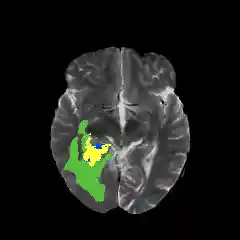

All MRI data was provided by the 2015 MICCAI BraTS Challenge, which consists of approximately 250 high-grade glioma cases and 50 low-grade cases. However, due to the limited time Each dataset contains four different MRI pulse sequences, each of which is comprised of 155 brain slices, for a total of 620 images per patient. Professional segmentation is provided as ground truth labels for each case. Figure 1 is an example of a scan with the ground truth segmentation. The segmentation labels are represented as follows:

Figure 1: Ground truth segmentation overlay on a T2 weighted scan.MRI Background